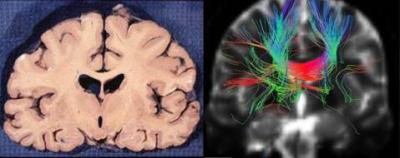

At present, fiber tracking algorithms are divided into deterministic tractography and probabilistic tractography. In deterministic algorithms, scholars proposed the fiber assignment by continuous tracking algorithm, the tensor deflection algorithm, the tensorline algorithm. Deterministic algorithms track fibers mainly depending on diffusion direction; however, they are susceptible to noise and partial volume effects, which result in the accumulation of tracking errors. Probabilistic algorithms can effectively reduce noise and partial volume effects, thus decreasing the accumulated errors and providing more fiber orientations. Unfortunately, their calculations are very complicated, time-consuming and easy to produce additional ambiguous fibers, which make the application of these algorithms difficult. In response to these phenomena, Shan Jiang and colleagues from School of Mechanical Engineering, Tianjin University proposed the tri-linear interpolation algorithm for white matter fiber tracking. A recent study from Jiang et al, published in the Neural Regeneration Research (Vol. 8, No. 23, 2013), selected a patient with acute infarction of the right basal ganglia and designed experiments based on either the tri-linear interpolation algorithm or tensorline algorithm. Fiber tracking in the same regions of interest (genu of the corpus callosum) was performed separately. The validity of the tri-linear interpolation algorithm was verified by quantitative analysis, and its feasibility in clinical diagnosis was confirmed by the contrast between tracking results and the disease condition of the patient as well as the actual brain anatomy. Statistical results showed that the maximum length and average length of the white matter fibers tracked by the tri-linear interpolation algorithm were significantly longer. The tracking images of the fibers indicated that this method can obtain smoother tracked fibers, more obvious orientation and clearer details. Tracking fiber abnormalities are in good agreement with the actual condition of patients, and tracking displayed fibers that passed though the corpus callosum, which was consistent with the anatomical structures of the brain. Therefore, the tri-linear interpolation algorithm can achieve a clear, anatomically correct and reliable tracking result.

Article: " Tri-linear interpolation-based cerebral white matter fiber imaging," by Shan Jiang1, Pengfei Zhang1, Tong Han2, Weihua Liu1, Meixia Liu1 (1 School of Mechanical Engineering, Tianjin University, Tianjin 300072, China; 2 Medical Image Evaluation Center, Tianjin Huanhu Hospital, Tianjin 300060, China)

Jiang S, Zhang PF, Han T, Liu WH, Liu MX. Tri-linear interpolation-based cerebral white matter fiber imaging. Neural Regen Res . 2013;8(23):2155-2164.